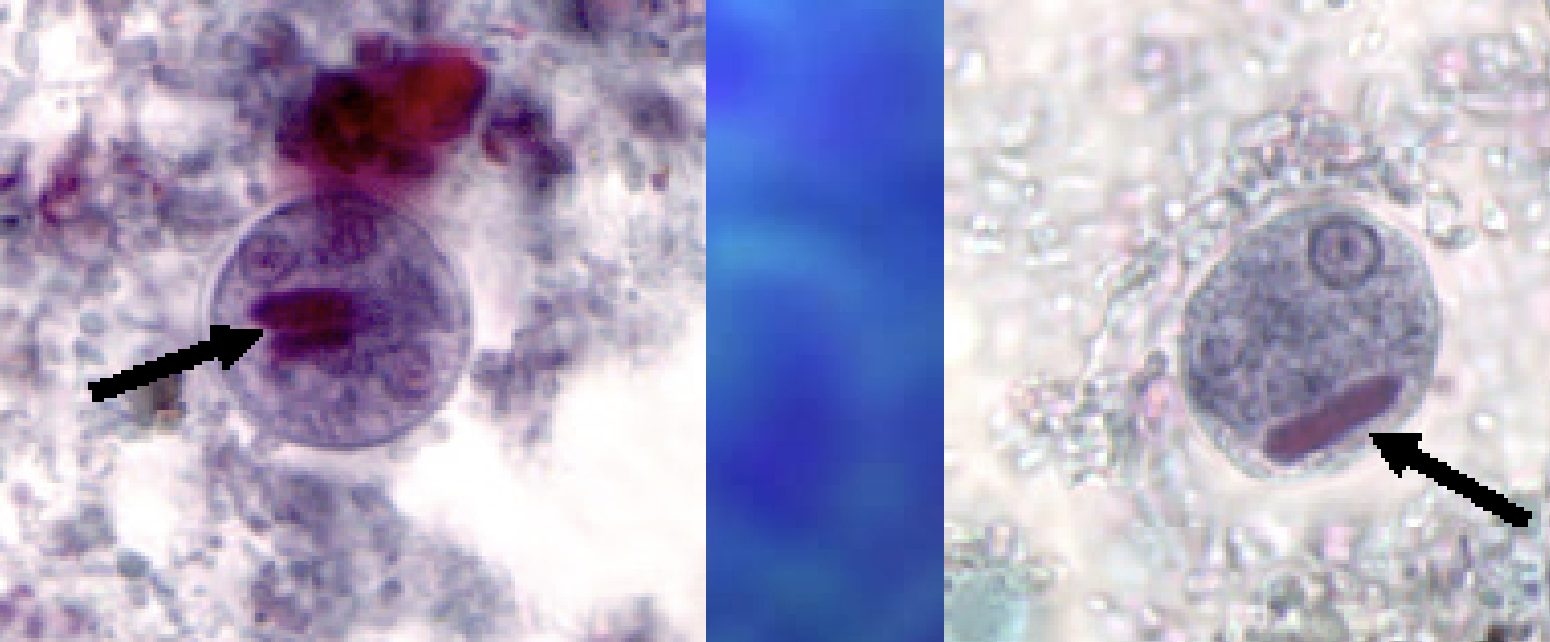

E. polecki cyst form may contain and inclsion body is it glycogen?

no

E. polecki cyst form

Iodamoeba butschlii cyst

Iodamoeba butschlii cyst